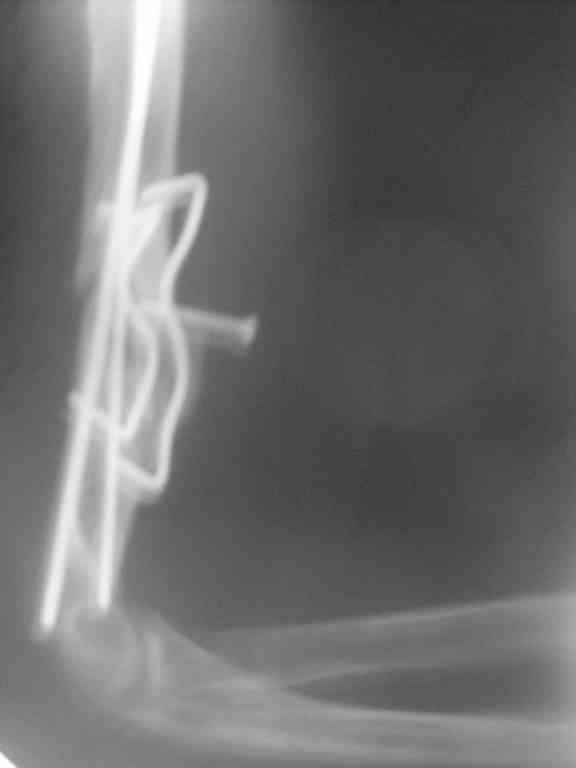

Добрый день. я вам звонил на днях. мне 24года, я из Башкирии. у меня следующая проблема: 19мая 2009г. я сломал правое плече в области нижней трети с повреждением лучевого нерва. провели операцию( пластина с шурупами) через несколько месяцев после рентген снимка обнаружили, что конструкция развалилась, образовался ложный сустав. провели вторую операцию( пучком спиц) безграмотно. проходил в ортезе 4 месяца. затем уехал в другой регион и там сделали мне следующую операцию: открытая репозиция с моделирующей резекцией отломков плечевой кости, невролиз лучевого нерва, интрамедулярный комбинированный остеосинтез плечевой кости двумя титановыми штифтами прямоугольного сечения с биоэнертным диэлектрическим покрытием и двумя компрессирующими скобами из NITI с термомеханической памятью формы, костная аутопластика зоны ложного сустава по типу "вязанки хвороста" из гебня подвздошной кости с фиксацией винтом, лавсановыми лигатурами. тендопластика лучевых разгибателей за счет круглого пронатора. Далее 4мес. иммобилизации. рентген снимки каждый месяц показывали что конструкция на месте. в январе сделал снимок и обнаружили что винт начал вылазить. ( снимок пралагается) лечащий врач сказал что необходима операция методом установки аппарата илизарова. Какие еще варианты операций у меня есть? сам склоняюсь к интерлокингу

Нужно для начала увидеть нормального качества снимки в двух проекциях, от плечевого до локтевого суставов.